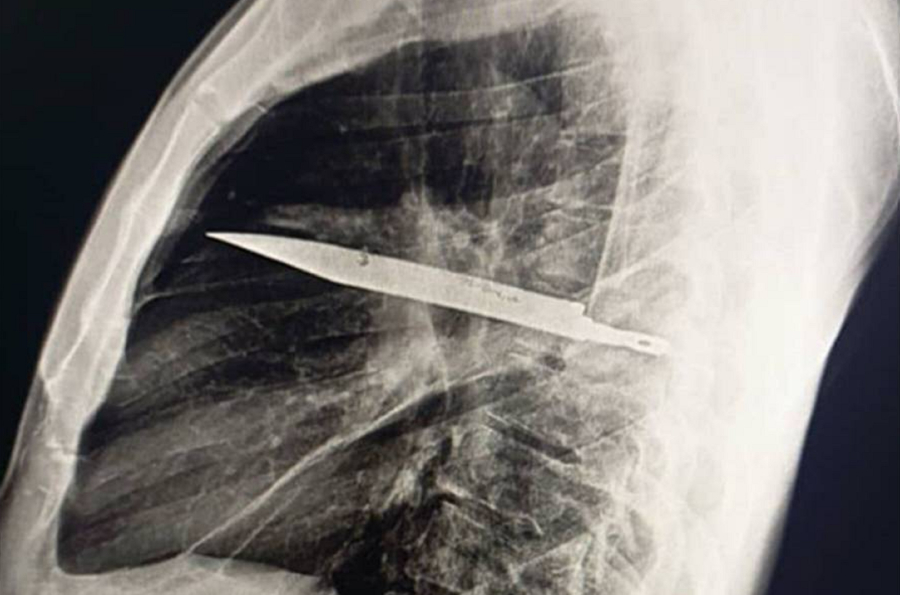

Στα οχτώ χρόνια που ακολούθησαν είχε μία «ομαλή πορεία» μέχρι να προκύψει το πρόβλημα που τον έκανε να πάει στον γιατρό. Η ακτινογραφία έδειξε «μεταλλικό αντικείμενο»- ένα μαχαίρι- στο στήθος του. Είχε εισέλθει από την ωμοπλάτη και το περιέβαλε πύον και νεκρωτικός ιστός.

Αμέσως οι γιατροί έκαναν χειρουργική επέμβαση και αφαίρεσαν το μαχαίρι. Έπειτα από δέκα ημέρες ο 44χρονος πήρε εξιτήριο. Οι ερευνητές σημείωσαν ότι «παρότι ανέρρωσε καλά μετά την επέμβαση, υπήρχε σημαντικός κίνδυνος» το γεγονός ότι το μαχαίρι είχε μείνει στο σώμα του να προκαλέσει τον θάνατό του.